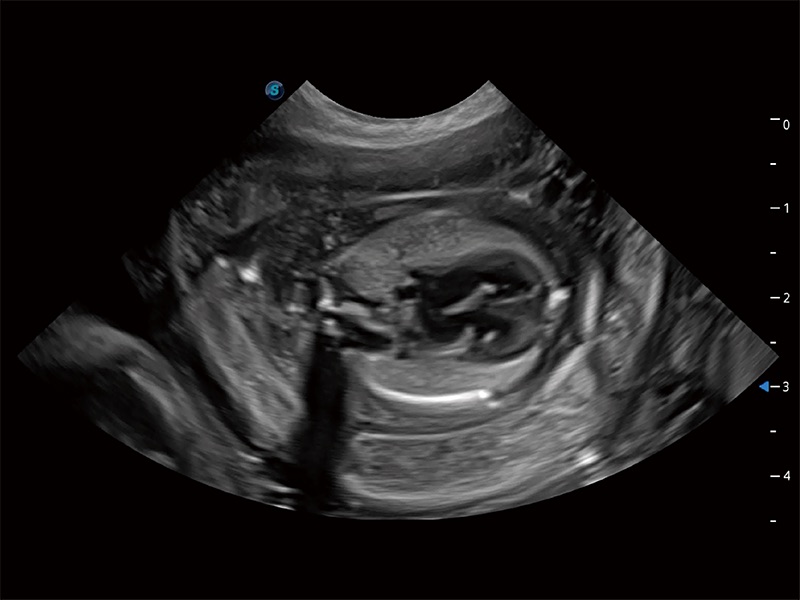

动物是人类最亲密的朋友和最值得信赖的伙伴。乐玩lewin国际也一直致力于探索动物专用的超声影像解决方案。全新推出的ProPet系列,是乐玩lewin国际在动物超声影像智能化、专业化、精准化的一次跨越式革新。动物不能用言语来表述自己的不适,通过超声影像,ProPet系列搭建了动物医生与不同物种沟通的“桥梁”,为动物医生注入了“治愈之力”。 ProPet 80 是乐玩lewin国际匠心打造的一款高端动物专用彩超,采用性能卓越的全新硬件架构,极大提升超声系统的运行效率和数据处理能力,帮助动物医生从容应对日益增多的挑战性病例和日益多样化的临床需求。

高性能和先进的临床应用工具可以为动物医生提供临床信心。ProPet 80 搭载了先进的腹部和浅表应用工具,帮助医生在日常临床实践中发挥前所未有的作用。

ProPet 80 专为动物医生设计,对不同的动物体型和生理结构作出了针对性的优化。通过动物影像专用软件,可满足个性化的应用需求,帮助动物医生获得更精确的诊断数据。

ProPet 80 全新的动物超声智能软件和丰富的探头群,为动物医生提供了高清晰度和精细分辨率的图像,无论在宠物、马科、畜牧还是实验室动物等应用中都可以轻松应对,为您的日常工作带来满意的体验。